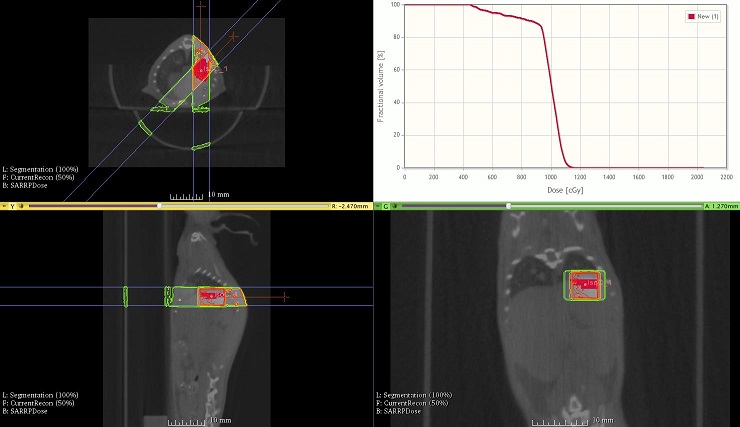

Advanced image guided pre-clinical radio surgery is facilitated by the Muriplan software. Muriplan not only controls the beam delivery, but is also a full pre-Clinical treatment planning system, featuring many functions you would expect to see on a clinical system. Muriplan guides the user through the treatment process of the CT imaging, image registration, dose planning, validation and delivery. The software is fully integrated with the SARRP controlling the X-Ray delivery, imaging and robotics. Muriplan eliminates the guesswork in pe-clinical irradiation studies by calculating the dose distribution, before you start treatment. The user can evaluate the isodose lines and Dose Volume Histogram for the contoured structures.